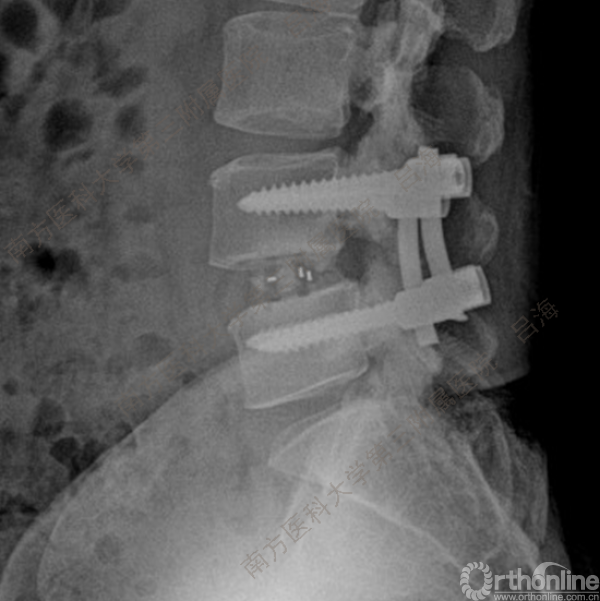

随着社会老龄化进程加快,胸腰椎退行性病变的治疗已经成为脊柱学术界的一个热点话题。MIS-TLIF手术可以治疗多种不同的胸腰椎退行性疾病,南方医科大学第三附属医院吕海教授结合病例为我们一一展示了该术式在治疗不同胸腰椎疾病时的具体手术过程。